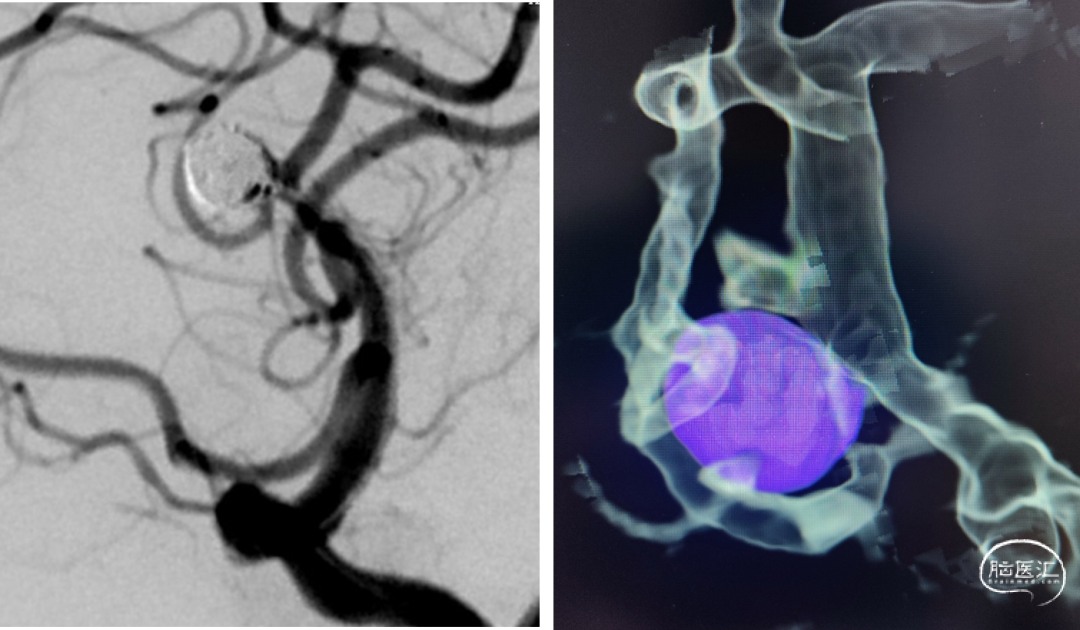

一般项目:患者女 年龄:71岁;

因“检查发现脑内动脉瘤10天”入院;

外院造影检查发现右侧大脑中动脉M1段动脉瘤、右侧颈内动脉眼动脉段动脉瘤。

既往史:既往有高血压、糖尿病病史。